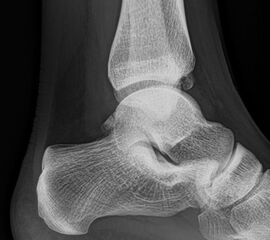

Sprunggelenk Mortise Aufnahme ohne Belastung (Mortise-View)

Positionierung:

• Zur Abbildung der Sprunggelenkgabel wird der Fuß 20° innenrotiert, um eine exakte ap-Abbildung der Malleolengabel zu erreichen.

• In dieser Aufnahme wird der mediale und laterale Gelenkspalt des Talus mit identischer Breite abgebildet.

• Innen- und Außenknöchel befinden sich in gleicher Distanz zum Röntgenfilm.

• Zentralstrahl wird mittig auf den Gelenkspalt am oberen Sprunggelenk zentriert.

Kennzeichen des Röntgenbildes:

• Darstellung des Talusdoms ohne Überlagerung.

• Das Sprunggelenk befindet sich dabei in 90° Stellung, um eine Überlappung des Kalkaneus mit der distalen Fibula zu vermeiden.

• Der Weichteilmantel ist erkennbar.

Besondere Bemerkungen zum Beispielbild:

• Die Innenknöchelfraktur ist deutlich besser nachvollziehbar als bei der ap Aufnahme (siehe vorheriges Bild).

• Keine Stufe im Gelenk.

• Die Wachstumsfugen sind noch erkennbar, im Wesentlichen aber geschlossen.

Zur Vollansicht und zum Lesen der Bildbeschreibung bitte die Bilder anklicken.